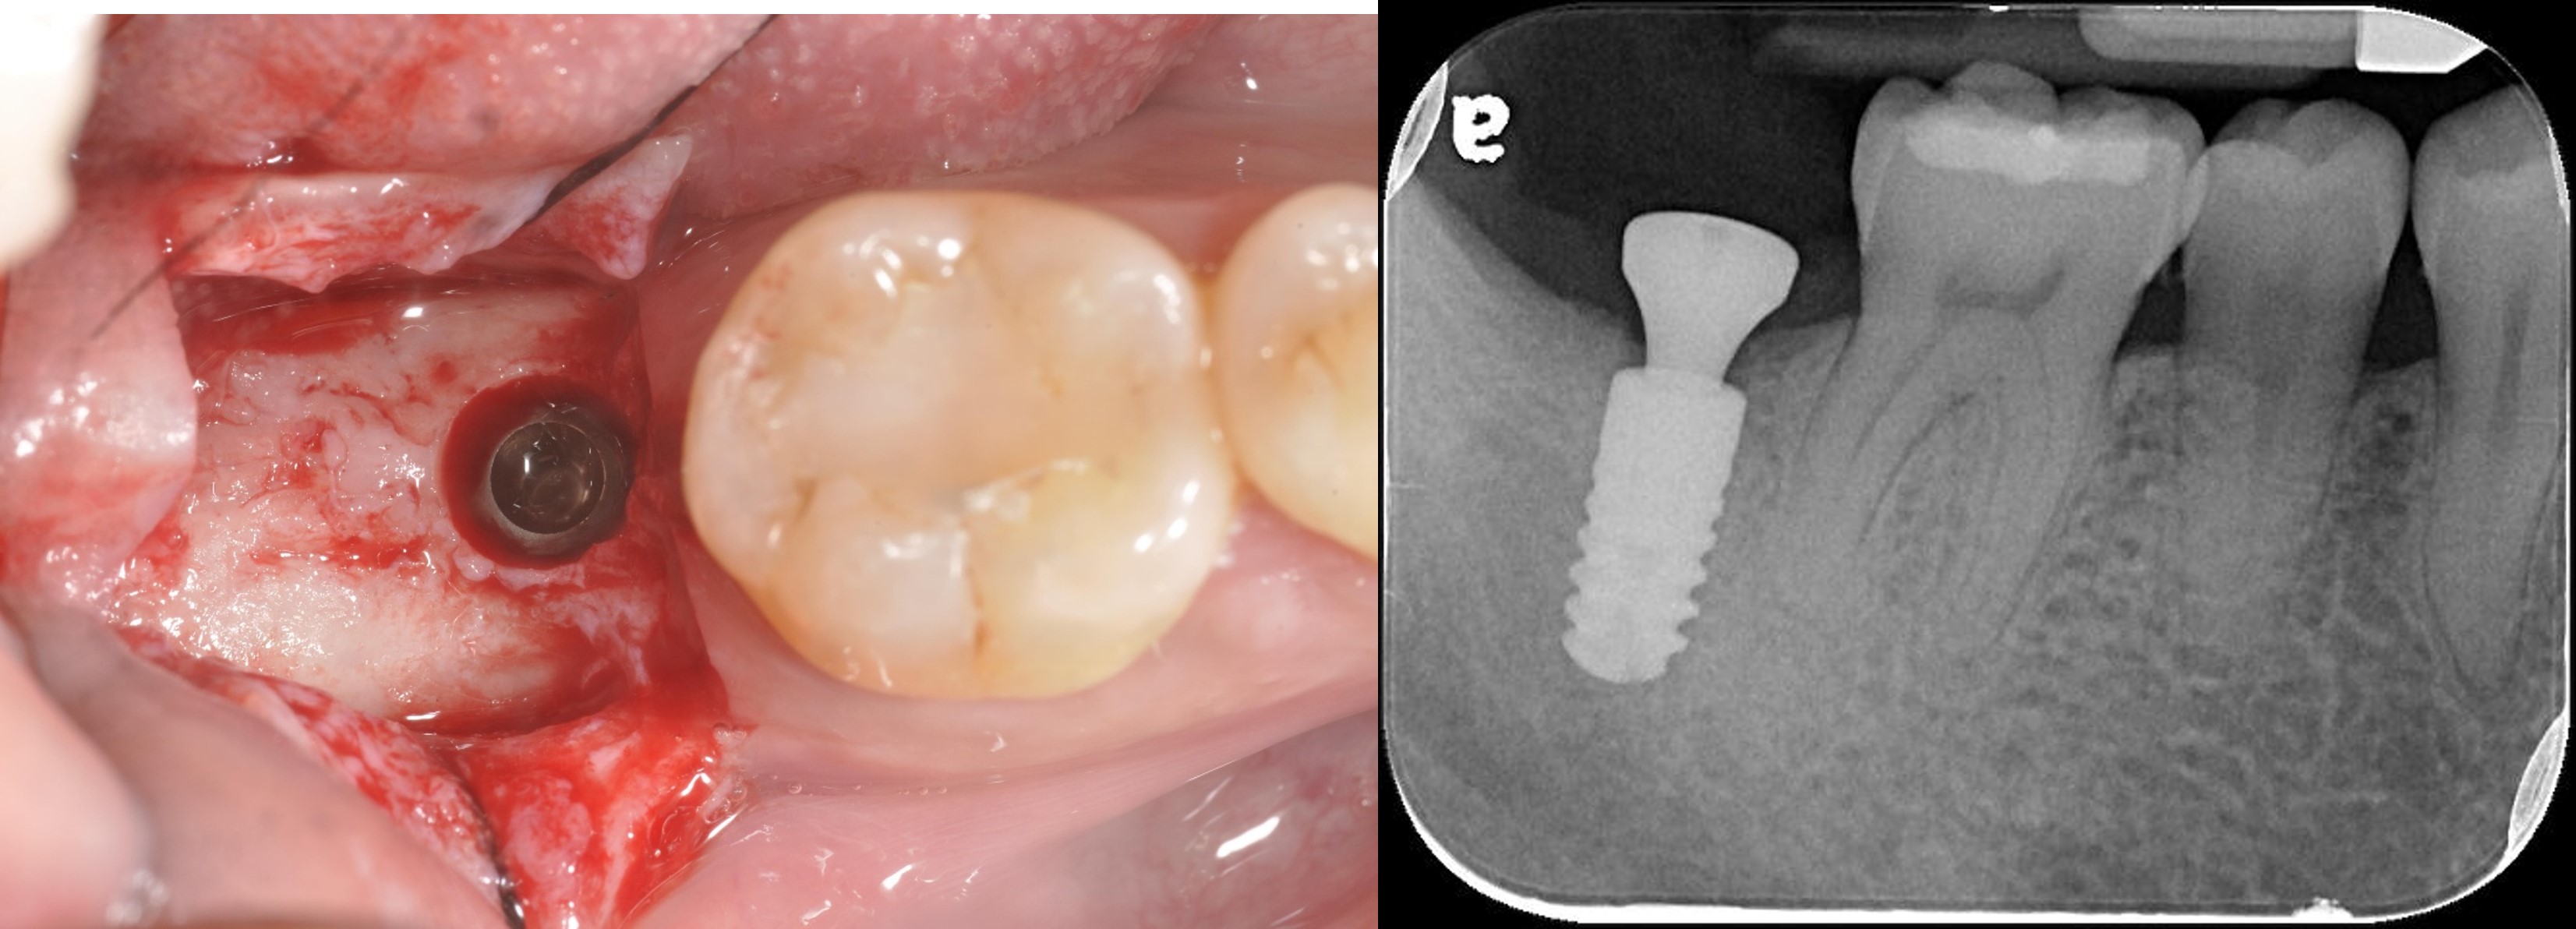

拔牙後進行骨脊保存術

導航定位器

手術模板

植牙